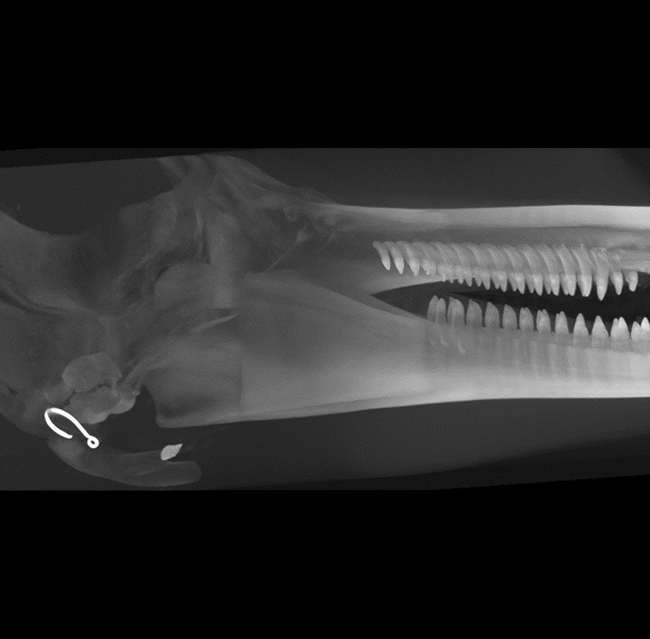

Our High Definition Volumetric Imaging (HDVI) technology is the most advanced form of Flat Panel CT technology. It delivers high-quality diagnostic imaging for both hard and soft tissues. This technology includes specific presets and customizable accessories designed for aquatic animals.

Outstanding image quality in hard and soft tissues with a spatial resolution up to 100 μ.